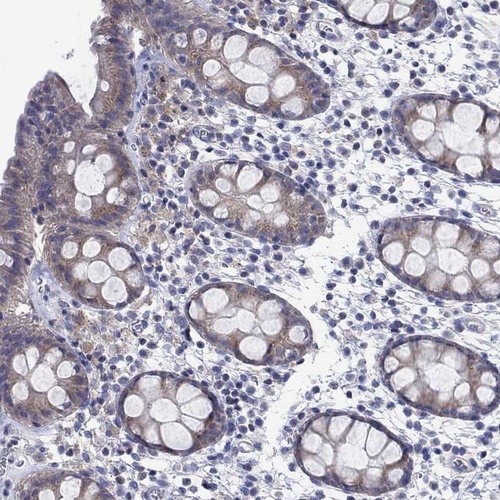

Immunohistochemistry analysis in human esophagus and rectum tissues using Anti-SULT2B1 antibody. Corresponding SULT2B1 RNA-seq data are presented for the same tissues.